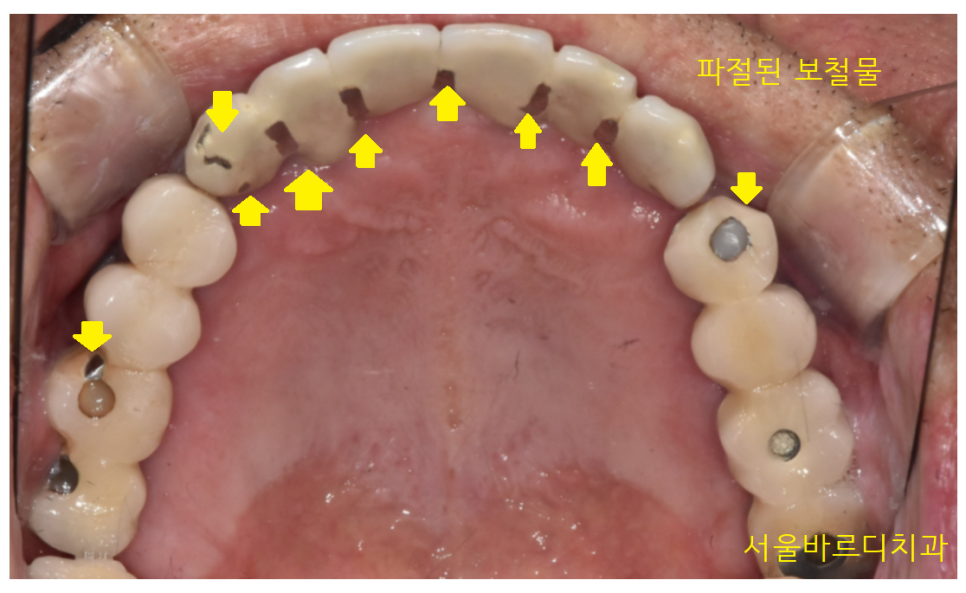

겉으로 보기에도 보철이 깨지고

오래된 흔적들이 보이네요~

안쪽에서 봐볼까요~?

23.04.14

안쪽에서는 씹는 부위다 보니 더 많이 깨졌습니다.

보철물이 다 깨질 때까지

오래 쓰셨습니다.